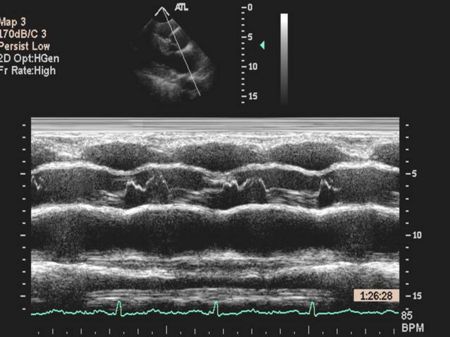

Ventricular M-mode

- Ventricular Wall Thickness

- Ventricular Chamber Size

- Intraventricular Masses